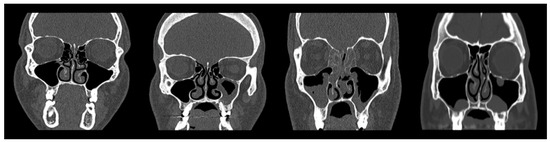

Following quality control, two experienced radiologists were engaged to manually evaluate and label the maxillary sinus findings into four distinct classes: Normal Maxillary Sinus (Normal MS), Opacified Maxillary Sinus (Opacified MS), Polyposis, and Retention Cysts. A visual illustration of the classification is presented in Figure 3, The first column (form left) column shows a normal sinus, the second column depicts partial opacification (Opacified MS), and the third and fourth columns represent Polyposis and Retention Cysts, respectively.

Recognizing that visual interpretation of CT images can be subjective, and different radiologists may interpret images differently based on their experience, interobserver variability was expected. To formally measure the level of agreement, Cohen’s Kappa [38] was employed, resulting in a substantial agreement (k = 0.821). Based on mutual consensus, the collected images were reliably categorized into the four predefined classes.

Figure 3. CT samples illustrating representative cases from each diagnostic category.